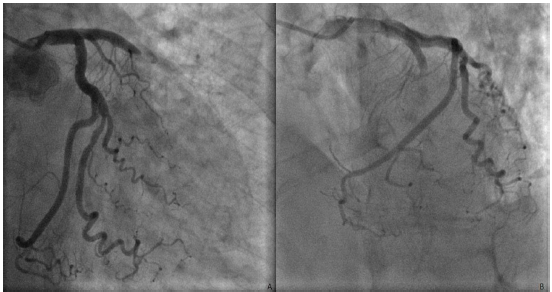

Mulher de 65 anos, hipertensa, diabética e dislipidêmica em acompanhamento regular e previamente assintomática, é atendida na emergência de um hospital terciário devido à dor torácica retroesternal súbita em aperto, de início há 50 minutos após uma discussão familiar. Relata uso prévio de metformina, dapaglifozina, atorvastatina e valsartana, negando outras comorbidades.

Ao exame: acordada, com fáscies de dor aguda, taquipneica em ar ambiente, sem esforço, sudoreica, corada, acianótica. FC: 96 bpm; PA: 146x90 mmHg no braço direito e 150x88 mmHg no braço esquerdo. MVUA com crepitação fina nas bases bilateralmente. Ritmo cardíaco regular em 3 tempos (B4), bulhas normofonéticas, sem sopros ou turgência jugular patológica a 90º. Pulsos radiais simétricos. O ECG de admissão está abaixo.

Em seguida, a paciente foi imediatamente encaminhada para a hemodinâmica, apresentando apenas a alteração demonstrada nas seguintes incidências:

Considerando o quadro clínico, o eletrocardiograma e a coronariografia apresentados, o diagnóstico da paciente é